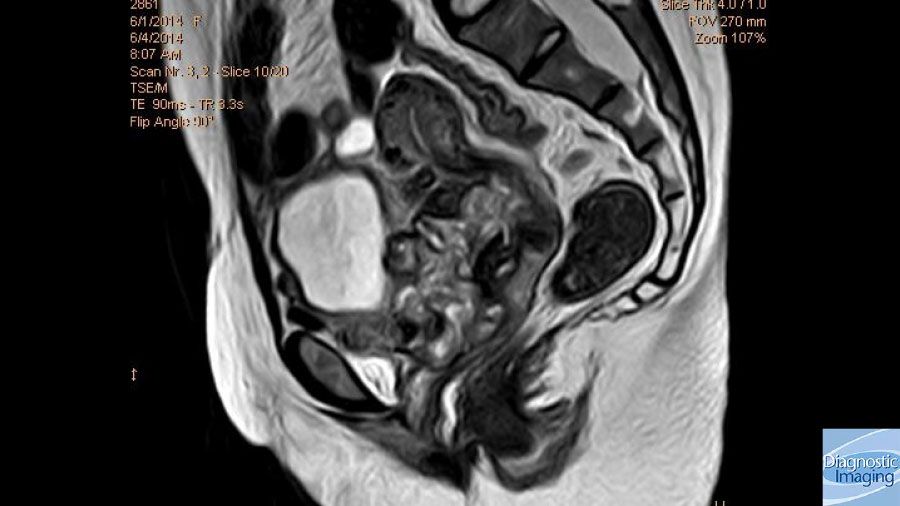

Postmenopausal Bleeding Pelvic Pain